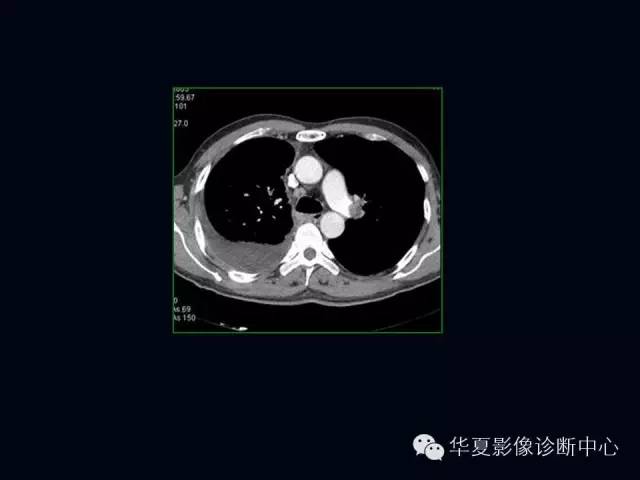

肺部血管性疾病

【PPT】肺部血管性疾病